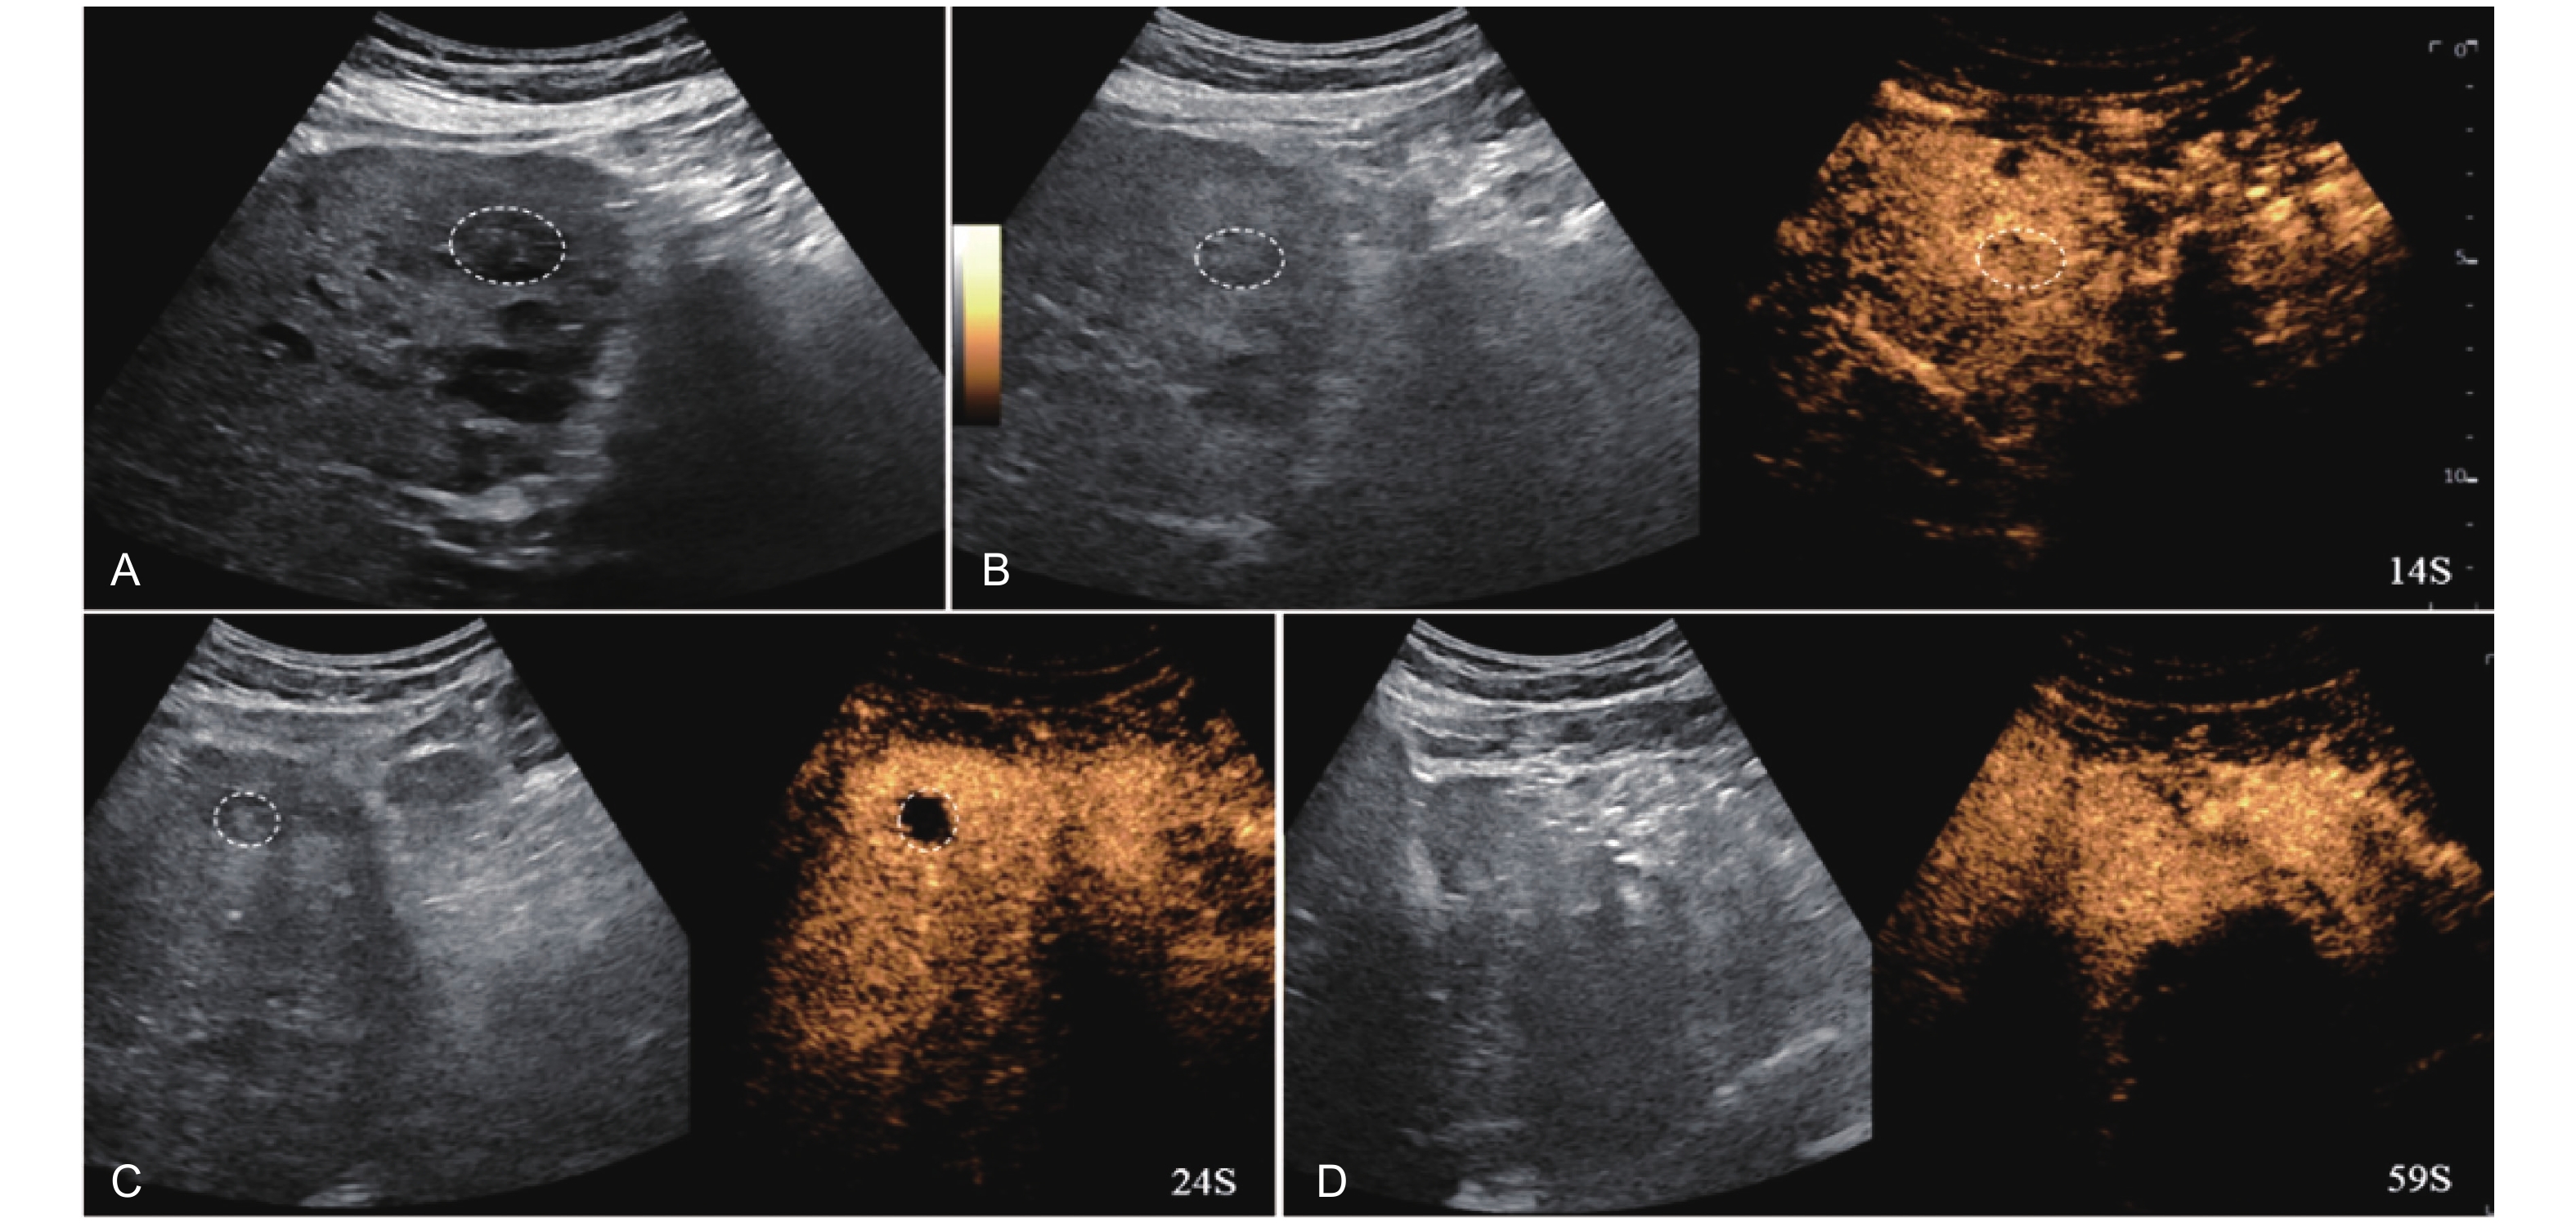

Figure 5

LR-TR Equivocal. Example of a treated tumor 36 days after TACE. (A) B-mode image shows a hypoechoic lesion (thick arrow) with ill-defined margins, measuring 36 mm in segment V; (B-C) CEUS shows intralesional ringlike hypoenhancement with early mild washout in the arterial phase; (D) The lesion shows ringlike hypoenhancement with marked washout in the portal venous phase; (E) The lesion shows complete washout in the late phase. Perilesional enhancement remains identical to the surrounding liver parenchyma throughout all phases. Findings are consistent with LR-TR Equivocal."